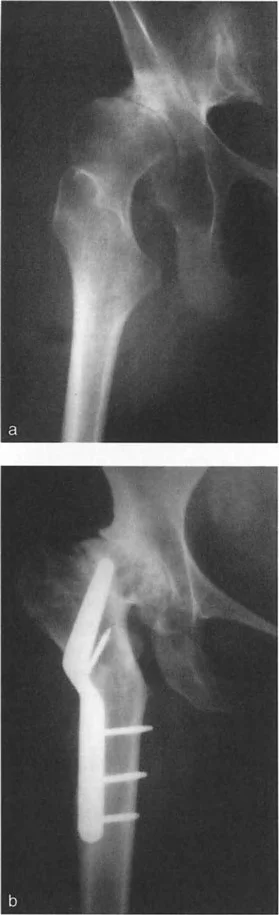

استبدال مفصل الركبة بعد فشل قطع عظم الظنبوب العلوي (HTO)

تُعد هذه الحالة من أكثر السيناريوهات تحديًا. بينما تكون عملية التحويل إلى استبدال مفصل الركبة بسيطة نسبيًا في حوالي 80% من الحالات، فإن الـ 20% المتبقية تمثل تحديات استثنائية. تاريخيًا، كانت معدلات فشل استبدال مفصل الركبة بعد HTO تتراوح بين 20% و 36% في متابعة 5 إلى 7 سنوات. لتجنب هذه النتائج السيئة، يجب على الجراح تقييم عوامل سريرية وإشعاعية بدقة قبل الجراحة.

- قطع عظم على مرحلتين أو متزامن: يتم إجراء قطع عظم رسمي إضافي أسفل الحدبة الظنبوبية لتصحيح المحور الميكانيكي.

- مرحلي: يتم تصحيح التشوه أولاً باستخدام مثبت خارجي أو صفيحة، ويُترك ليلتئم، ثم يتم إجراء استبدال مفصل الركبة القياسي بعد أشهر. هذا أكثر أمانًا للأنسجة الرخوة ولكنه يتطلب عمليتين جراحيتين كبيرتين.

- متزامن: يتم إجراء قطع العظم واستبدال مفصل الركبة في نفس الوقت. يمكن غالبًا استخدام ساق الظنبوب لمفصل الركبة كجهاز تثبيت داخل النخاع لقطع العظم.